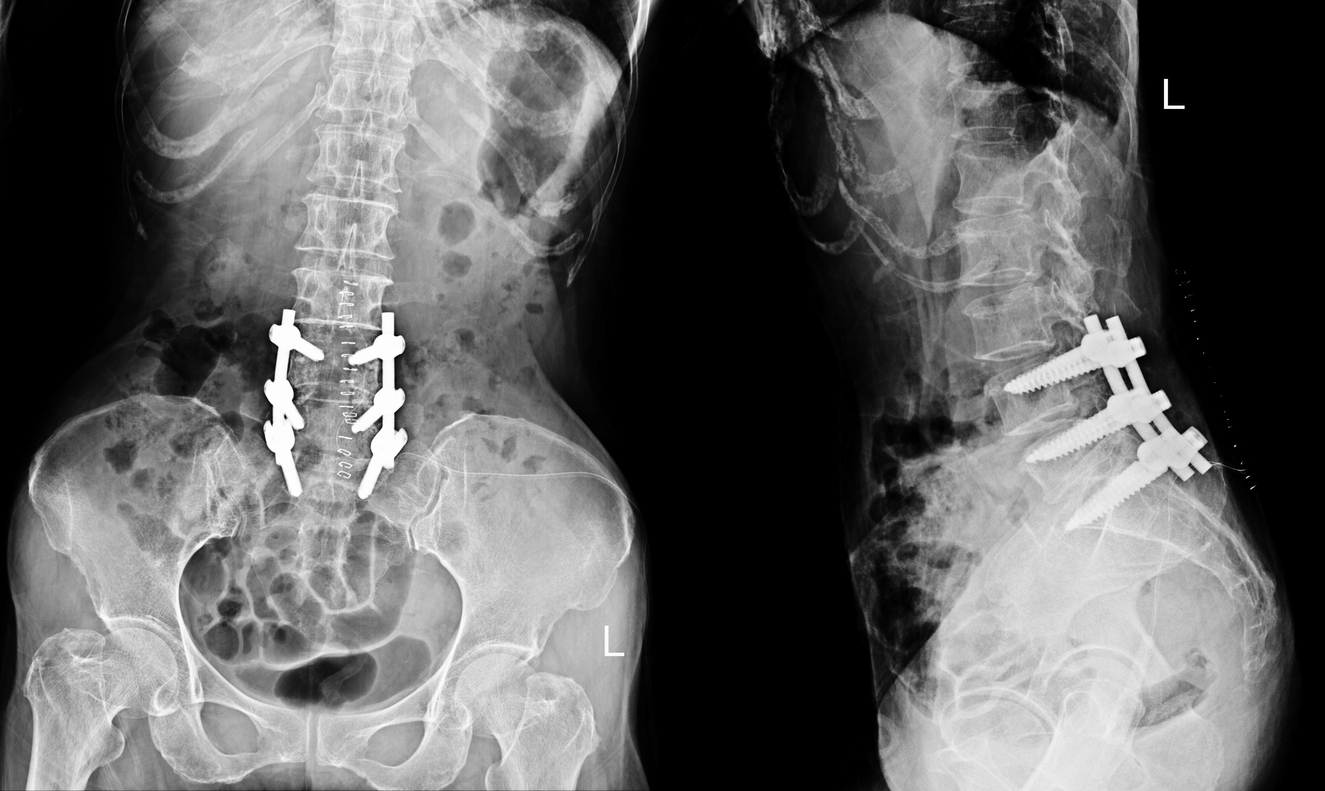

Spinal fusion involves joining specific bones in the spine (vertebrae) using bone grafts, screws, rods, or plates to promote natural bone healing and solid fusion. It’s performed to treat painful conditions where movement between vertebrae causes discomfort or nerve compression. Over time, the fused vertebrae heal into a single, solid bone, providing long-term stability and significant pain relief.

4. Bone Graft Placement: Bone grafts and implants (screws, rods) are positioned to stabilize the spine.